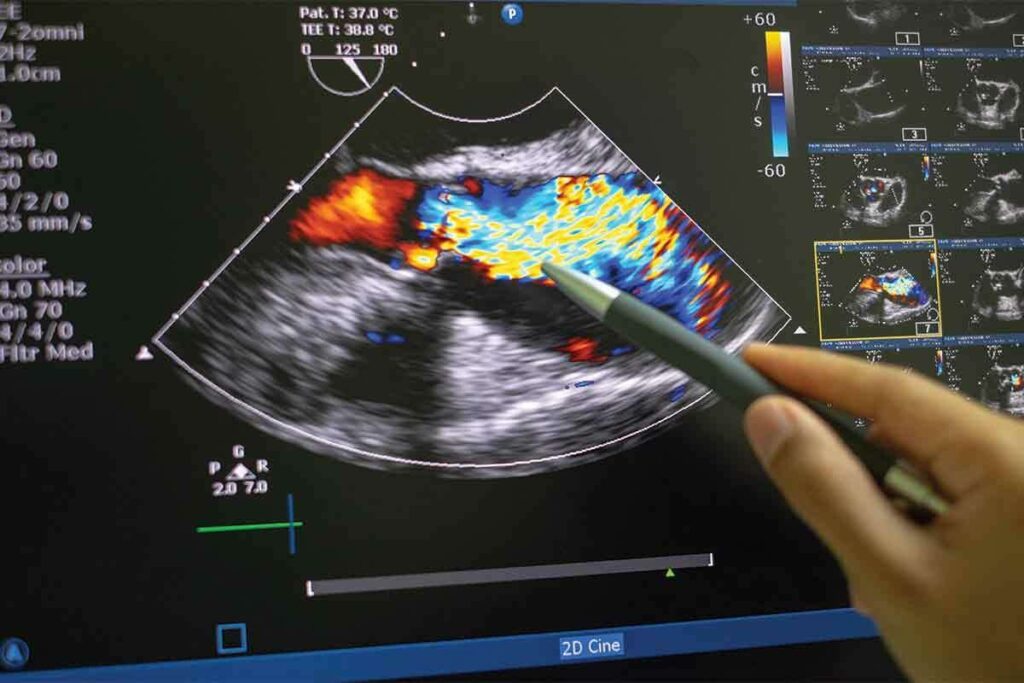

Gamma Cameras and Image Capture Technology

A gamma camera is used to capture images. It detects the gamma rays from the radiopharmaceuticals. As the kidneys absorb the radiopharmaceuticals, the camera takes pictures of their structure and function. This is key for spotting kidney problems like blockages or poor function.